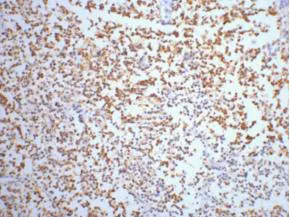

AFP alpha 1 Fetoprotein(17C5)Mouse Monoclonal Antibody

Cat: AMM06666

Size1:50μL Price1:$118

Size2:100μL Price2:$220

Size3:200μL Price3:$380

Application:WB,IHC-P,IF-P,IF-F,ICC/IF

Reactivity:Human

Conjugate:Unconjugated

Optional conjugates: Biotin, FITC (free of charge). See other 26 conjugates.

Gene Name:AFP